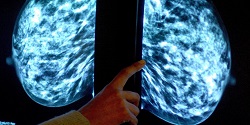

دانشمندان میگویند بعضی از مواد شوینده خانگی، ضد عفونیکنندهها و حشره کشها از جمله عواملی است که میتواند به شکل گیری سرطان تهاجمی سینه در زنان منجر شود.

به گزارش فارس به نقل از یاهونیوز، یافتههای پژوهشگران نشان می دهد قرار گرفتن در معرض مواد شیمیایی موجود در برخی مواد شوینده خانگی، ضد عفونی کننده ها و حشره کش ها خطر شکل گیری سرطان سینه را در زنان افزایش می دهد.

نکته مهم این است که سرطان سینه ای که بدین علت ایجاد می شود، بدخیم بوده و درمان آن نیز مشکل است. پژوهشگران انگلیسی می گویند این نوع مواد شیمیایی عامل شکل گیری 10 تا 20 درصد از کل موارد سرطان سینه در این کشور محسوب می شود.

سرطان سینه ای که بدین شکل ایجاد می شود، در برابر درمان های هورمونی مقاومت زیادی دارد و لذا برای مقابله با آن باید به سرعت از روش هایی همچون عمل جراحی، رادیودرمانی و شیمی درمانی استفاده شود. البته برای درمان موثرتر این نوع سرطان سینه هنوز باید روش های درمانی موثرتری ابداع شود.

محققان هشدار می دهند زنان باید برای درامان ماندن در برابراین نوع سرطان مهاجم، در زمان استفاده از مواد شوینده خانگی، ضد عفونی کننده ها و حشره کش ها احتیاط کرده و از تماس با این مواد یا استنشاق آنها به طور جدی خودداری کنند.